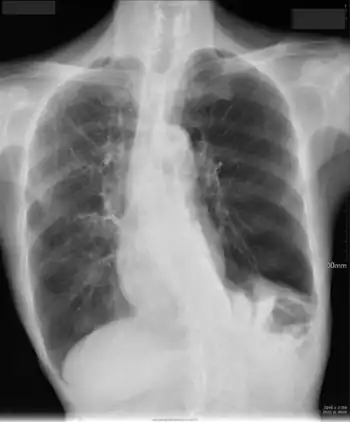

| Chest X-ray in a case of COPD exacerbation where a nasopharyngeal swab detected Haemophilus influenzae, with right-sided opacities | |

A chest X-ray is usually performed on people with fever and, especially, hemoptysis (blood in the sputum), to rule out pneumonia and get information on the severity of the exacerbation. Hemoptysis may also indicate other, potentially fatal, medical conditions.[6]